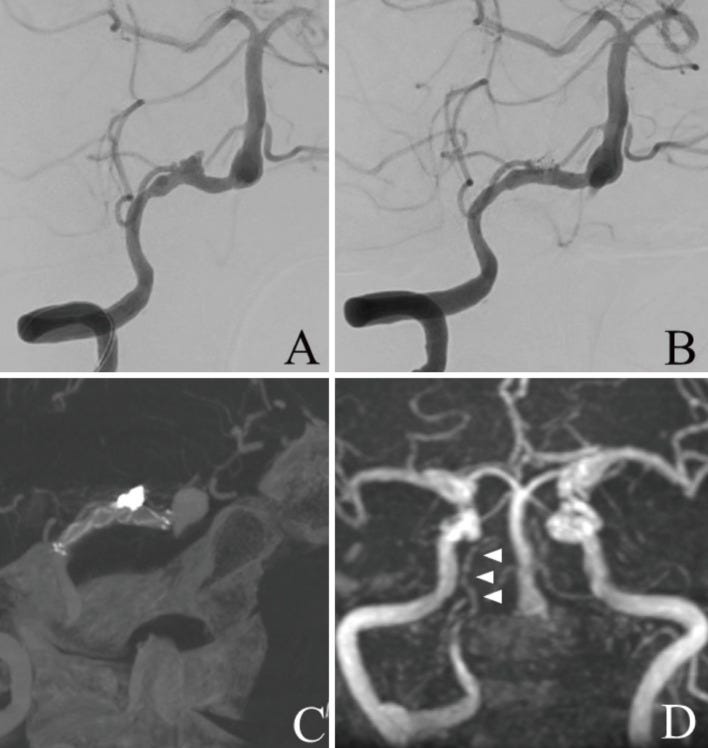

(A) Frontal view of the right vertebral artery angiography (VAG) before stent-assisted coil embolization shows dissecting aneurysm in the right vertebral artery (VA) involving the right posterior inferior cerebellar artery (PICA). (B) Frontal view of the right VAG after stent-assisted coil embolization shows coil occlusion of the aneurysmal sac and patency of the right VA and right PICA. (C) Cone beam computed tomography (CT) image shows the bladed stent placed across the dissecting lesion and coils deployed into the sac. (D) Postoperative magnetic resonance angiography (MRA) performed 2 weeks after treatment shows that the dissecting aneurysm is not visualized and the right PICA is patent.